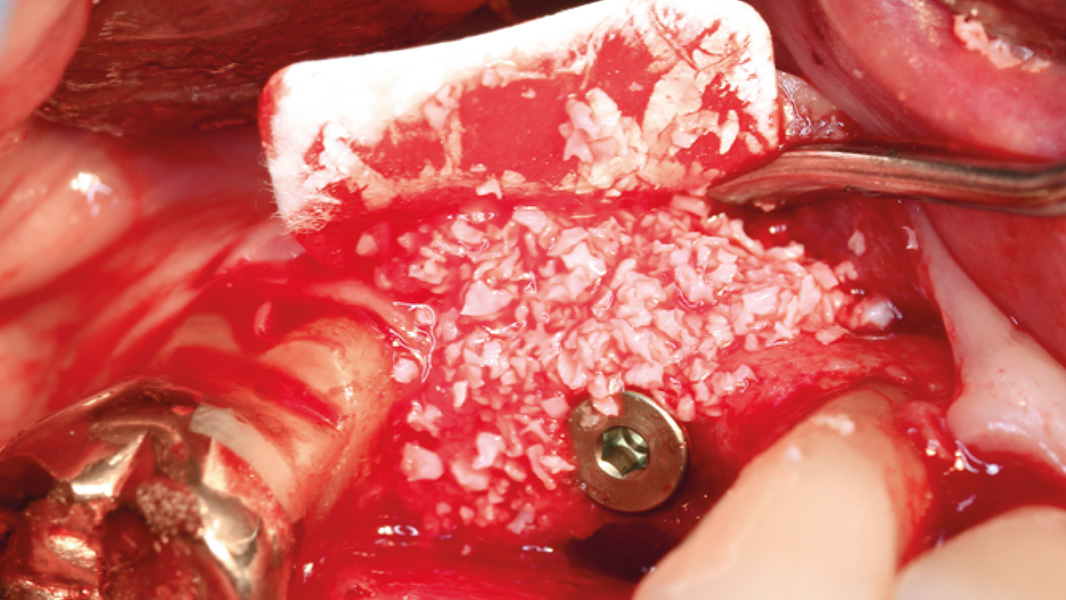

Schnelle und vorhersagbare Knochenregeneration, beobachtet bei der Implantation im zweizeitigen Therapieverfahren nach gesteuerter Knochenregeneration mit der Striate+.

- Eine frühe vertikale Knochenregeneration wurde 12 Tage nach dem chirurgischen Eingriff beobachtet.

- Rasche Zunahme der Knochenhöhe während der Heilungsphase

- Vertikale Knochenregeneration stabilisiert das Implantat, erhöht die Überlebensrate und das ästhetische Ergebnis.

Die Striate+ Kollagenmembran wird meist in Verbindung mit Knochenersatzmaterial oder patienteneigenem Knochen angewendet. Sie ist eine wirksame Barriere, um die Knochenregeneration im Defektraum zu ermöglichen. Die raue Oberfläche fungiert als optimale Leitschiene, um ein stabiles qualitativ besseres Knochenvolumen zu generieren.4